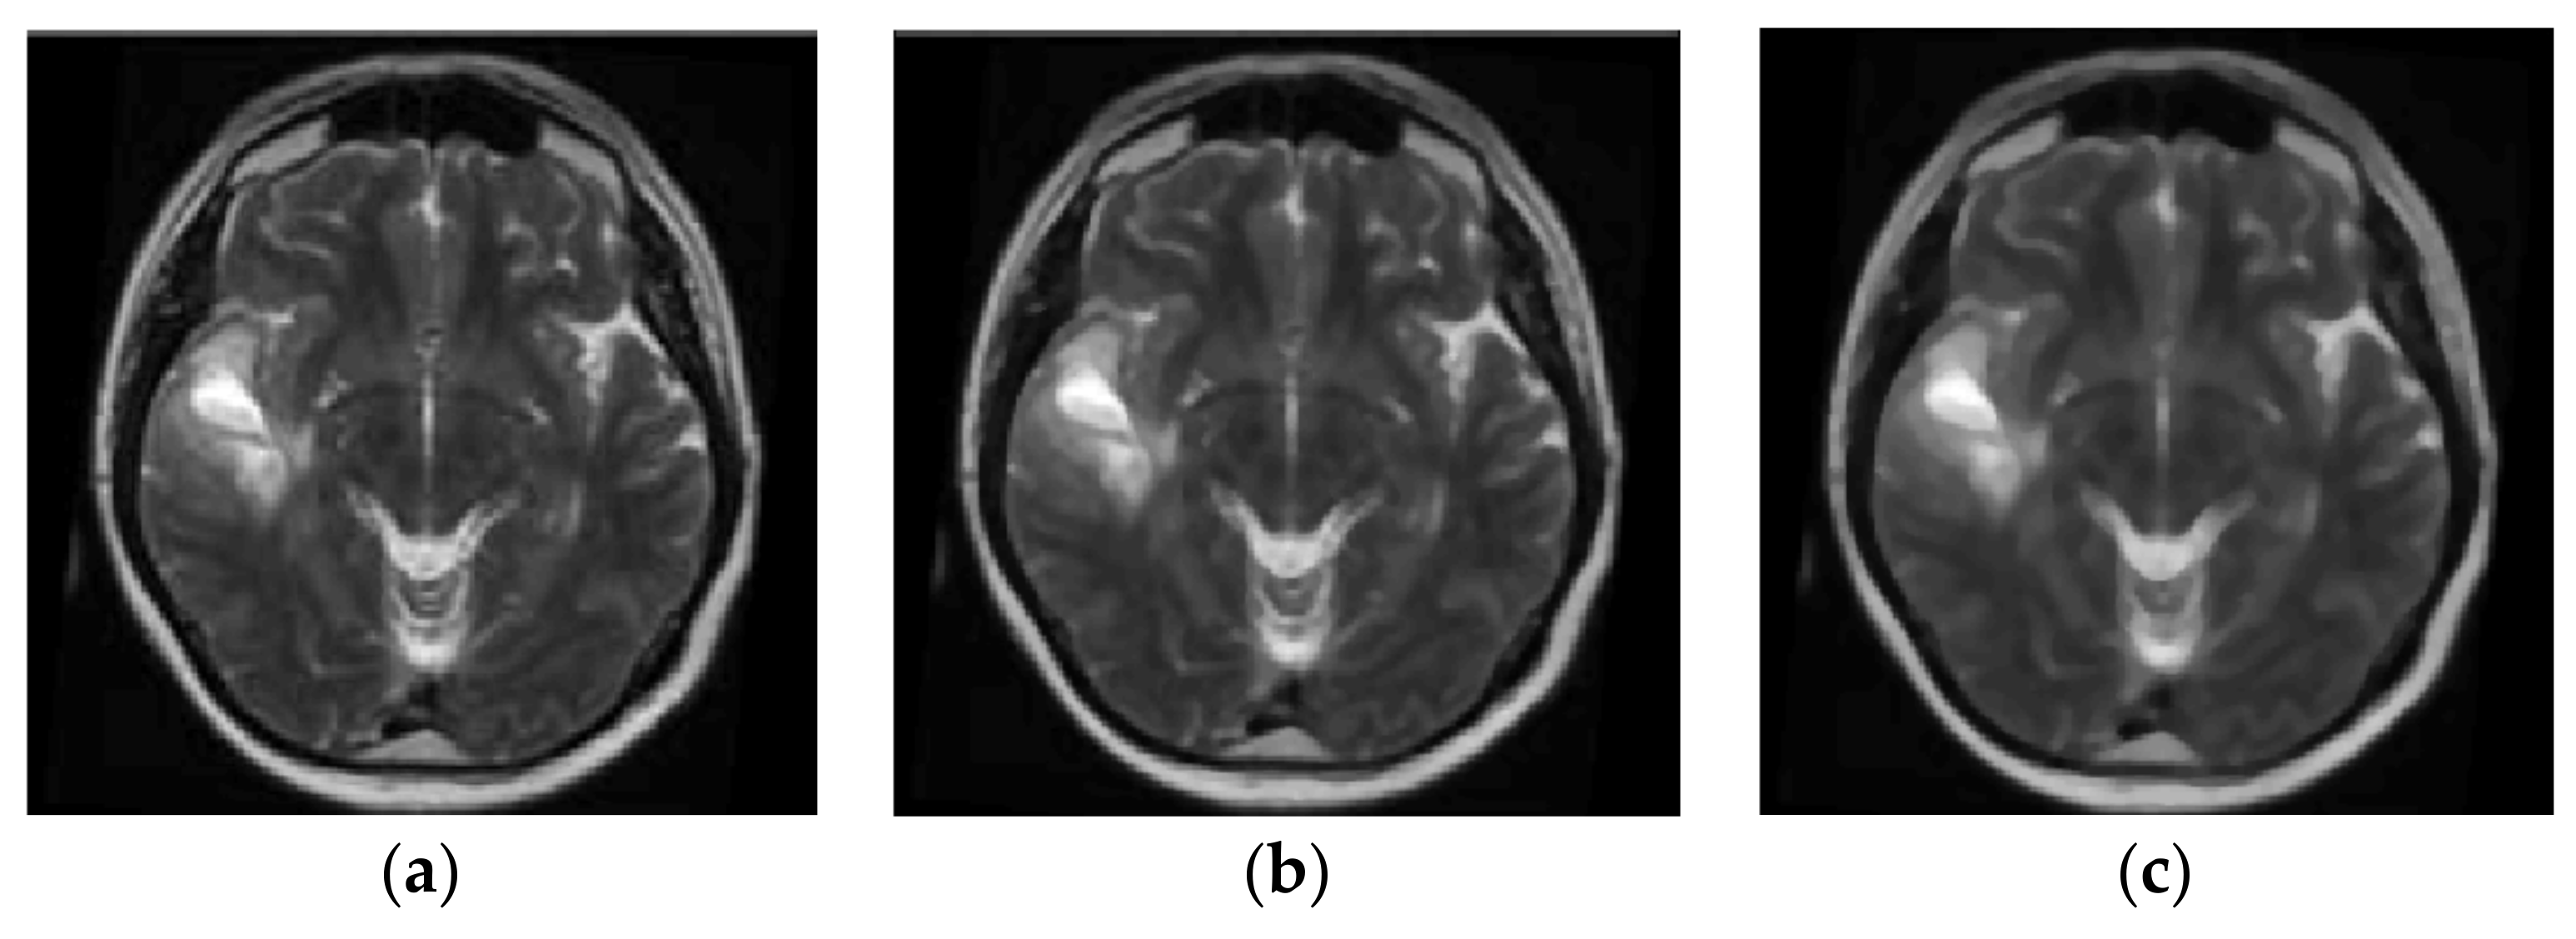

Brain magnetic resonance imaging (MRI) [5,6,7,8,9,10,11] can be used for the diagnosis of glioma, AIDS dementia, Alzheimer’s, cancer metastasis, etc. The image processing is applied to T1-weighted (T1-w) and T2-w MRI scans. T1-w MRI images are obtained during the T1 relaxation time when the 63% of the original net magnetization is reached after the end of the MRI scanner radiofrequency pulse. T2-w images are obtained during T2 relaxation time, which is the time required for the decline of net magnetization to fall down to the 37% of the original net magnetization [12]. Fluid-attenuated inversion recovery (FLAIR) is an adaptive T2-w image produced when the signal of brain edema and other structures with high water content are removed [8]. Brain tumors appear with lower intensity than normal brain tissue on T1-w images and higher intensity on T2-w images. The images used in these studies have been retrieved by public databases like the Alzheimer’s Disease Neuroimaging Initiative (ADNI) [13] public database (http://adni.loni.usc.edu/), the Human Connectome Project, WU-Minn Consortium, the Open Access Series of Imaging Studies (OASIS), the Harvard Medical School MRI Database, and other local hospital databases like the Al-Kadhimiya Teaching Hospital in Baghdad, Iraq.

In the preprocessing stage presented in [8], the MRI scan is enhanced by Gaussian low pass filtering for noise removal, normalization of pixel intensity and histogram stretch/shift to cover all grayscale and increase contrast. A histogram threshold is used to isolate the background while mid-sagittal plane of brain is detected and corrected before feature extraction and classification. In the post processing stage that follows the classification, tumor location identification by 3D boxes based genetic algorithm is applied as well as tumor segmentation by 3D active contour without edge (ACWE).

Co-occurrence matrices that are used in many referenced approaches represent mathematically the texture features as gray level spatial dependence of texture in an image. The co-occurrence matrix can be constructed based on the orientation and distance between image pixels. Texture patterns are governed by periodic occurrence of certain gray levels. Consequently, the repetition of the same gray levels at predefined relative positions can indicate the presence of a specific texture. Several texture features such as entropy, energy, contrast and homogeneity, can be extracted from the co-occurrence matrix. A gray level co-occurrence matrix C(i, j) is defined based on a displacement vector dxy = (δx, δy). The pairs of pixels separated by dxy distance that have gray levels i and j are counted and the results are stored to C(i, j). Such a co-occurrence matrix is defined in [29] for psoriasis detection using skin color and texture features. In [36], the co-occurrence matrix is also used to classify images based on texture analysis into one of the following skin disorders: eczema, impetigo, psoriasis. Modified Gray Level Co-occurrence Matrix (MGLCM) is used in [8] where the authors proposed this second-order statistical method to generate textural features of MRI brain scans. These features are used to statistically measure the degree of symmetry between the two brain hemispheres. Bayesian coring of co-occurrence statistics are used for the restoration of bicontrast MRI data for intensity uniformity in [5].